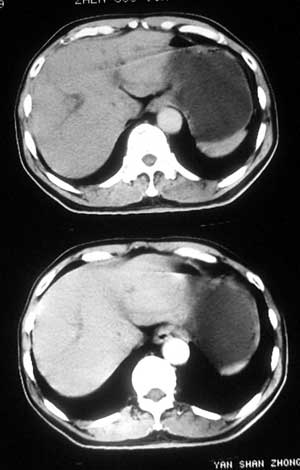

患者,男,57岁,梗阻性黄疸10余天。

这个病例胰头无明显增大,胆总管扩张明显而肝内胆管扩张更不明显,病程较短,

注意到十二指肠乳头明显突出,但尚光滑。分析以下可能性:

1、十二指肠乳头本身的病变,如乳头炎症;

2、急性乳头水肿,胆总管下端结石排石后乳头水肿;

3、壶腹部胆总管下端肿瘤累及十二指肠乳头。

十二指肠乳头粘膜慢性非特异性炎症